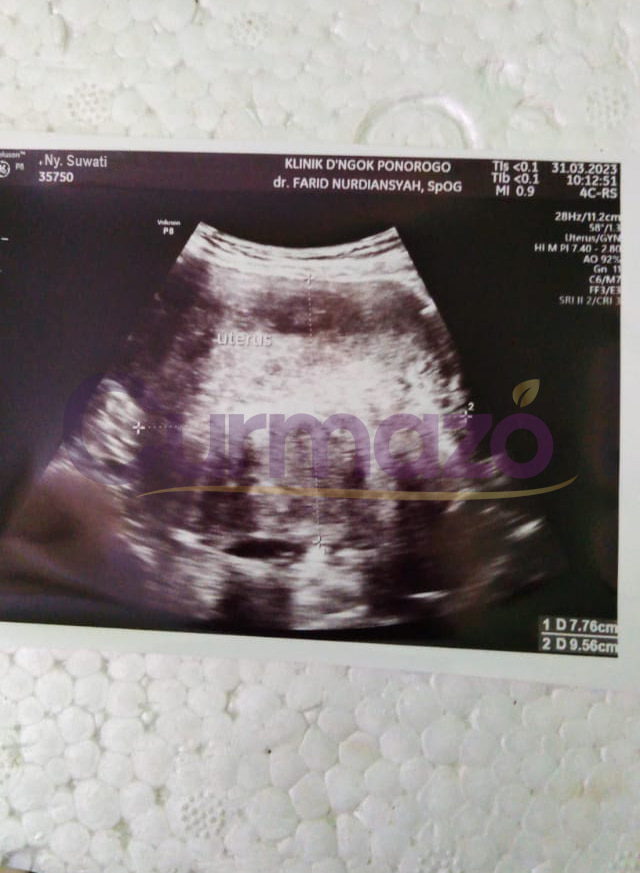

Sejak Maret 2023, saya merasakan penderitaan yang tak terbayangkan akibat kista dengan ukuran 7,76 x 9,56 cm. Haid yang tidak teratur, nyeri saat menstruasi, dan rasa ngilu di perut kiri bawah hingga pinggang membuat setiap hari menjadi tidak nyaman.

Hampir 4 bulan pengobatan saya sudah tidak merasakan gejala seperti sebelumnya, haid sudah lancar dan teratur. 8 Mei 2023 Saya coba menjalani pemeriksaan, hasilnya sangat luar biasa kista berukuran 7,76 x 9,56 cm tersebut hilang total.